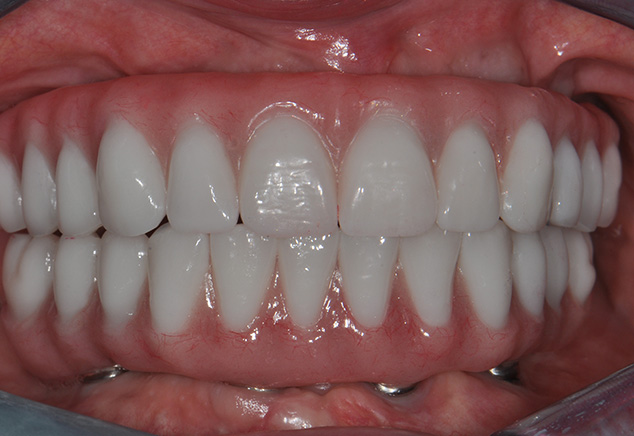

The next afternoon, the prostheses were inserted (Fig 10) and panoramic radiographic confirmation of proper seating was obtained (Fig 11). Any necessary occlusal adjustments were then completed. The patient was then seen every 2-3 weeks for deplaquing and plaque control review per our earlier discussed protocol. The occlusion was also refined as needed. A water irrigation device was given and reviewed at 6 weeks post-surgery.

At the insertion appointment, the healing caps were removed and cleaned with Chlorhexidine. Figure 15 demonstrates the excellent healing of the soft tissue prior to insertion of the prosthesis. Once inserted, the esthetics, phonetics, and OVD of the prosthesis were confirmed. The occlusion was adjusted as needed. Screws were tightened to 15 Ncm, screw access openings were filled with Teflon tape to within 2mm of the surface, and a soft material such as Telio or Fermit was used to seal the access. A maxillary acrylic nightguard was fabricated to aid in protection of the occlusal surfaces from wear and to help reduce any parafunctional habits. The completed case is shown (Fig 15, Fig 16, Fig 17, Fig 18). At subsequent appointments, the prostheses were evaluated to determine if they needed to be removed to assess the soft tissue or if any contouring of the acrylic was necessary. Eventually the soft material used to close the access can be replaced with a hard composite material.